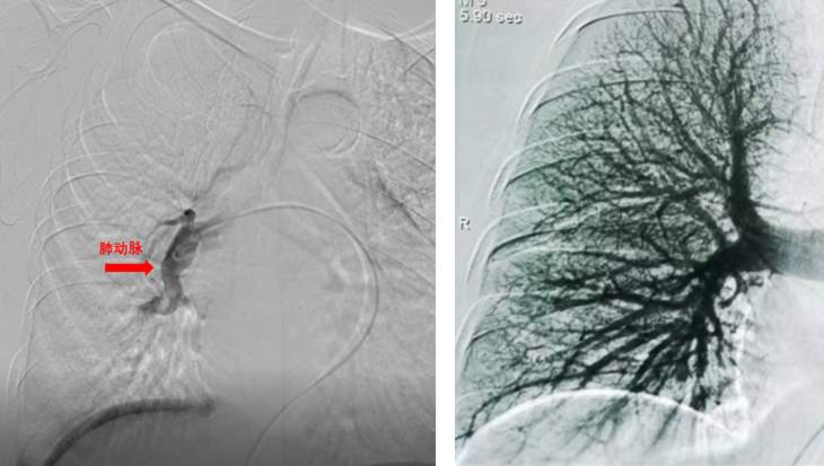

当天120急救送到了我们科室。只见王阿姨表情痛苦,口唇、指端明显紫绀,气喘得不能讲话,端坐在床上,无法躺平,双腿肿的很厉害。心率116次/分,血压90/50mmHg,血氧饱和度80-85%。急查血,氧分压49.4mmHg,心衰指标(NT-proBNP):15378pg/ml,D-二聚体:4219ng/ml,心电图示窦性心动过速。胸片提示肺动脉段突出,心影明显增大(图1)。

图1胸片